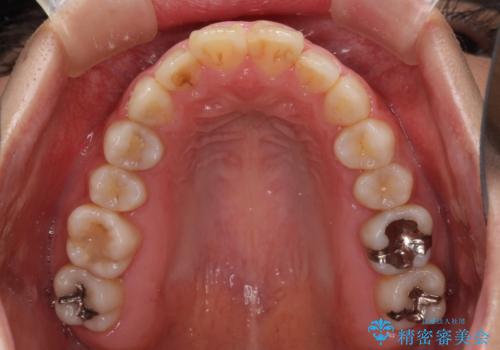

- ワイヤーではない矯正治療があると聞いたとのことで来院された患者様です。

長年前歯のデコボコを気にしていたもののワイヤー矯正に抵抗があり躊躇していたそうですが、インビザラインなら治療してみたいとのことで相談にいらっしゃいました。

インビザライン適用の歯列であったため、歯と歯の間を削るIPRを用いて改善することとしました。

お仕事柄、長時間のマウスピース装着が苦ではなかったので、歯列はすぐに整いましたが、ゆっくりとした交換頻度であったので、2年ほどの治療期間を要しました。